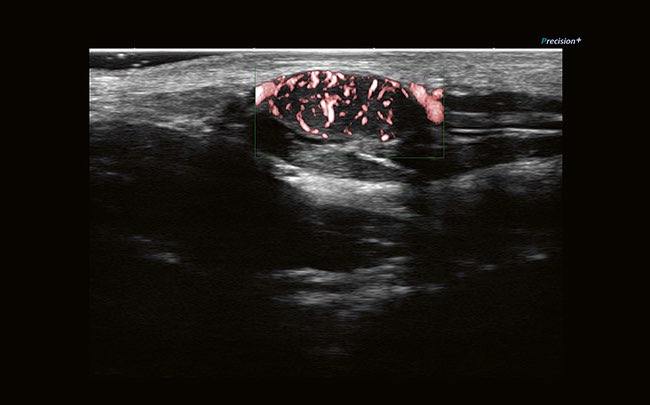

- Технология Precision Imaging

Технология Precision + позволяет получать однородные изображения, четкие углы и контуры.